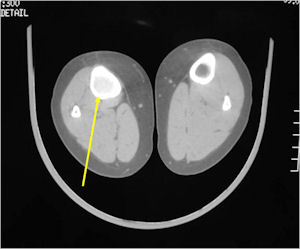

CT Scan:

- Well defined nidus with a smooth peripheral margin; +/- mineralization (CT more sensitive than XR and MRI for detecting mineralization); CT is better for detecting nidus in presence of exuberant sclerosis

- Today, most osteoid osteomas are amenable to CT guided percutaneous radiofrequency ablation (RF Ablation). This is a minimally invasive technique in which the patient is put under general anesthesia and the nidus is localized under a CT scan. A needle is placed in the nidus and then the nidus is burned by means of radiofrequency waves. It is over 90% successful and there are minimal risks. Most patients notice that the pain is gone the very next day. There is little down time and most patients return to normal activities within a day or two.